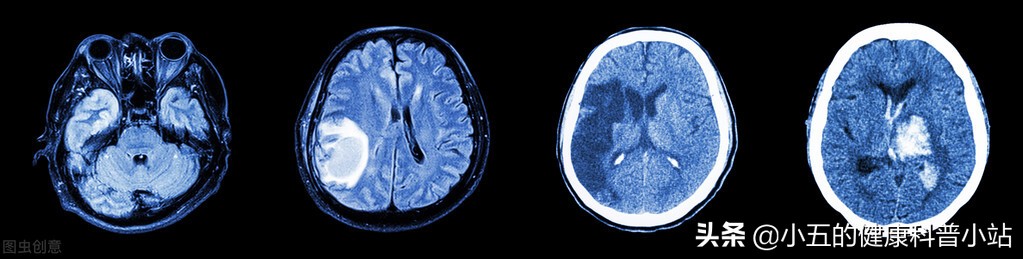

3、脑梗死

临床研究表明心脑宁胶囊可以用于治疗脑梗死恢复期和后遗症期,可以有效改善脑梗死患者的临床症状,加快其运动功能和语言功能的恢复,并且可以改善其记忆力和协调性,从而尽可能的恢复脑梗死患者的生活能力。

临床上在常规治疗的基础上加用心脑宁胶囊,可以稳定颈动脉粥样硬化斑块,降低其破裂的风险,促进斑块硬化和消解,从而有效改善颈动脉的供血状态,改善大脑供血,同时降低血栓脱落的风险,对于预防中风、心肌梗死具有重要作用。